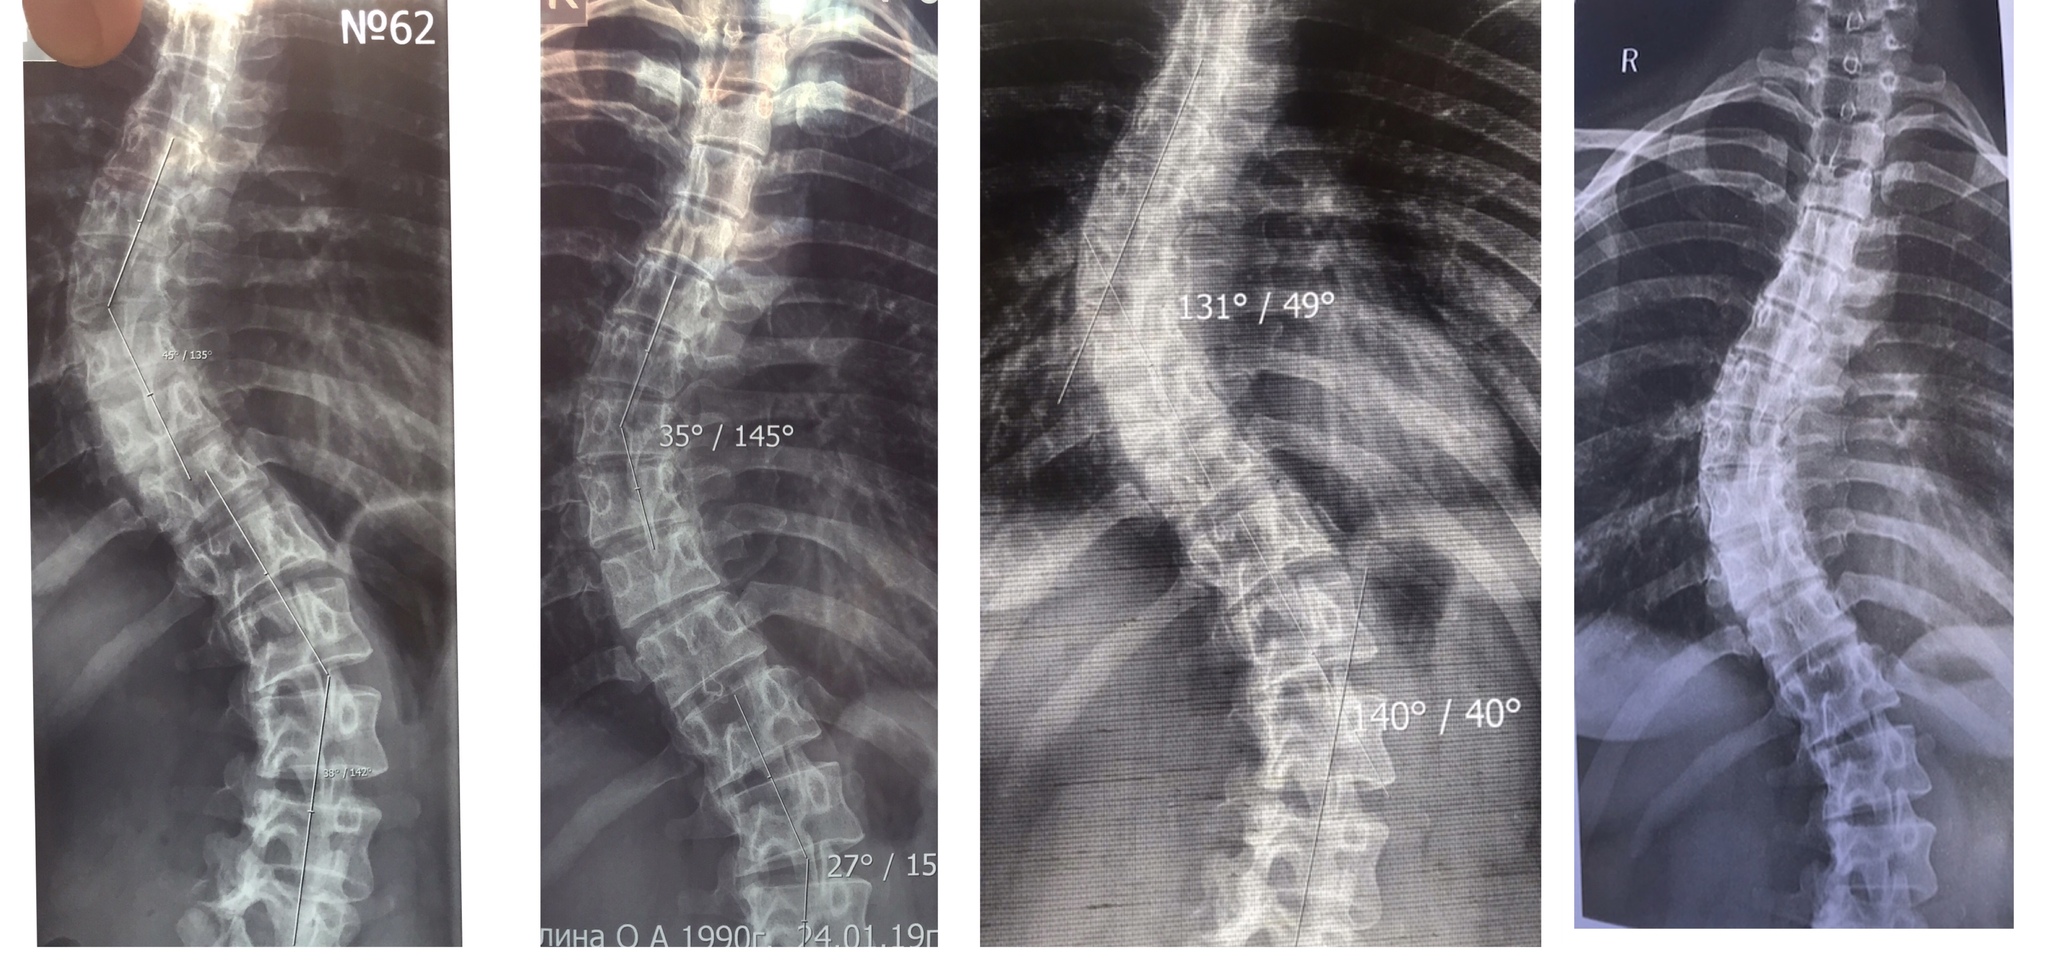

слева направо: 2018, 2019, 2020, 2021. Потом я перестала делать снимки так часто. Последний я не забрала, есть только описание. В 2021 в грудном 40 гр и 12 в поясничном. В 2024 в грудном 39 гр., а поясницу я не сделала